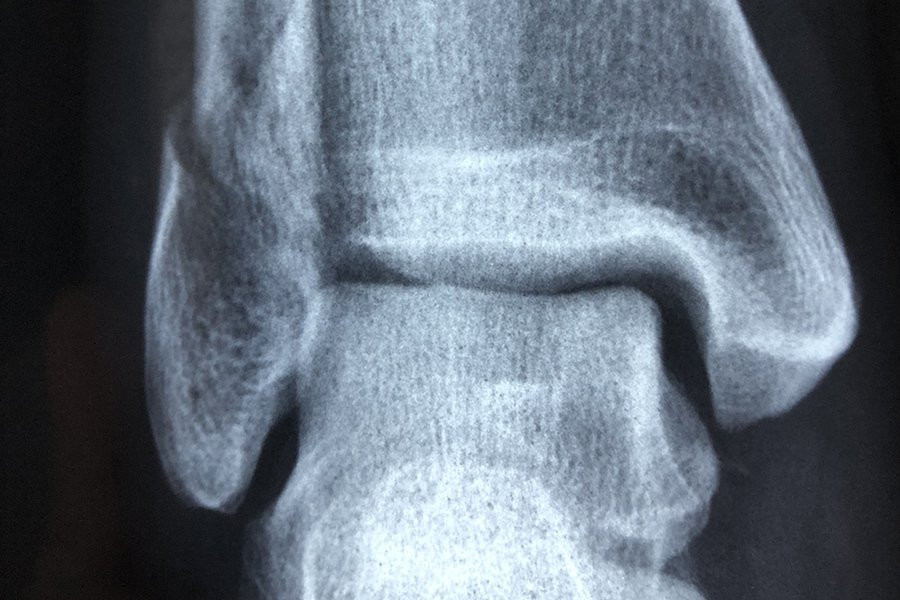

Форма коленной чашечки человека может быть индикатором того, подвержен ли он большему риску развития остеоартрита, согласно новому исследованию Австралийского национального университета (ANU). Исследование было опубликовано в журнале Osteoarthritis and Cartilage.

Исследовательская группа приступила к изучению того, может ли форма коленной чашечки быть способствующим фактором.

Используя передовые методы анализа изображений для создания 3D-моделей сотен костей коленной чашечки, команда затем применила методы моделирования формы для визуализации и измерения формы поверхностей коленной чашечки в трех измерениях.

Хотя они не нашли уникальных особенностей среди коленных чашечек женщин по сравнению с мужчинами, они обнаружили изменения в поверхностях коленной чашечки, которые были более выражены у людей с остеоартритом.

«Удивительно то, что различные суставные поверхности коленной чашечки по-разному меняют форму при остеоартрите и по мере увеличения тяжести заболевания», — сказала Уилсон.